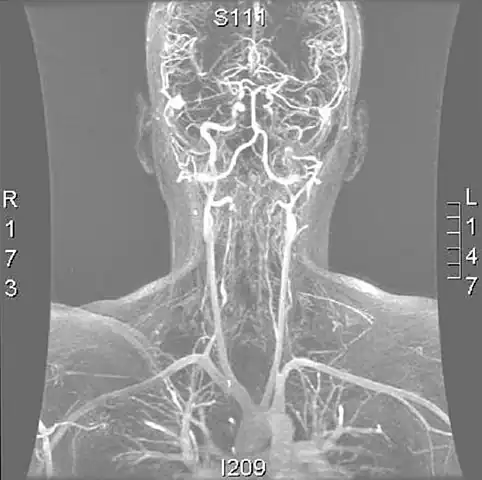

Various diagnostic modalities exist to demonstrate blood flow or absence thereof in the vertebral arteries. The gold standard is cerebral angiography (with or without digital subtraction angiography).[4][14][15] This involves puncture of a large artery (usually the femoral artery) and advancing an intravascular catheter through the aorta towards the vertebral arteries. At that point, radiocontrast is injected and its downstream flow captured on fluoroscopy (continuous X-ray imaging).[16] The vessel may appear stenotic (narrowed, 41–75%), occluded (blocked, 18–49%), or as an aneurysm (area of dilation, 5–13%). The narrowing may be described as "rat's tail" or "string sign".[2] Cerebral angiography is an invasive procedure, and it requires large volumes of radiocontrast that can cause complications such as kidney damage.[16] Angiography also does not directly demonstrate the blood in the vessel wall, as opposed to more modern modalities.[2][3] The only remaining use of angiography is when endovascular treatment is contemplated (see below).[2]

More modern methods involve computed tomography (CT angiography) and magnetic resonance imaging (MR angiography). They use smaller amounts of contrast and are not invasive. CT angiography and MR angiography are more or less equivalent when used to diagnose or exclude vertebral artery dissection.[14] CTA has the advantage of showing certain abnormalities earlier, tends to be available outside office hours, and can be performed rapidly.[2] When MR angiography is used, the best results are achieved in the T1 setting[3] using a protocol known as "fat suppression".[2][3][4] Doppler ultrasound is less useful as it provides little information about the part of the artery close to the skull base and in the vertebral foramina, and any abnormality detected on ultrasound would still require confirmation with CT or MRI.[2][3][4]